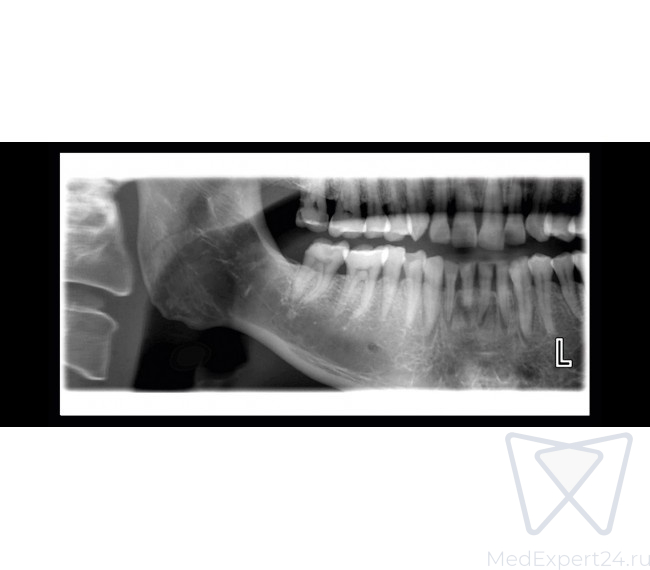

- Стандартная панорама взрослого,

- Стандартная панорама детская,